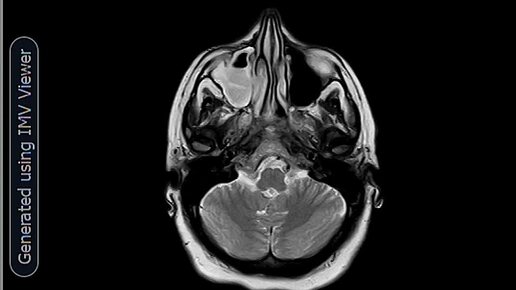

МРТ-Незаращение листков прозрачной перегородки(киста прозрачной перегородки)